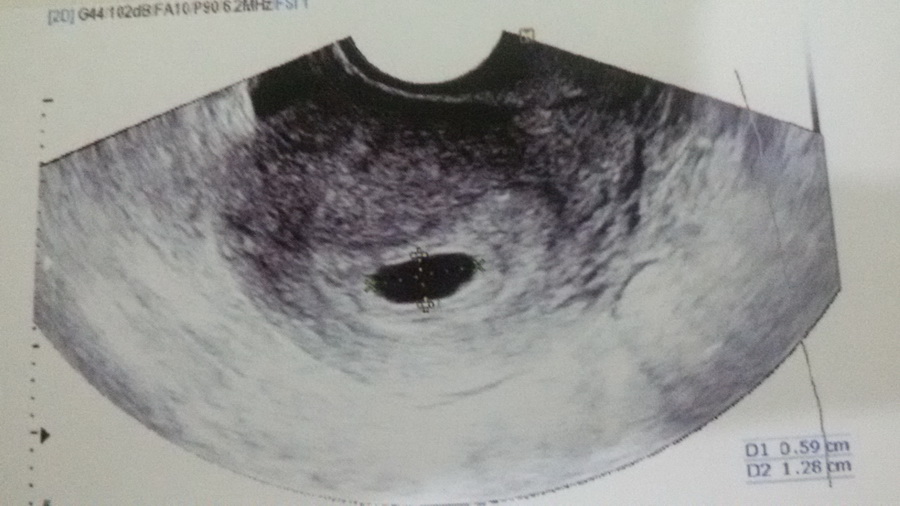

รูป U/S ครั้งล่าสุด

ผล U/S ทางช่องคลอด ครั้งที่ 3 วันที่ 21 ก.ย. เห็นถุงไข่แดง ทำให้เริ่มมีความหวังขึ้นมา

ครั้งนี้ (21 ก.ย.) ได้เจาะเลือดครั้งที่ 1 ฟังผลเลือดวันที่ 23 ก.ย. มีค่า BHCG 48,338 แล้วเจาะเลือดอีก ฟังผล วันที่ 28 ก.ย. ซึ่งผลเลือดมีค่า BHCG ลดลงเหลือ 45,971 แล้ว U/S ทางหน้าท้อง ซึ่งไม่เห็นตัวอ่อน หมอไม่ซาวด์ช่องคลอดแล้วค่ะ บอกผลชัดเจน ให้ยุติการตั้งครรภ์ ซึ่งนัดวันจันทร์ที่ 3 ต.ค. นี้